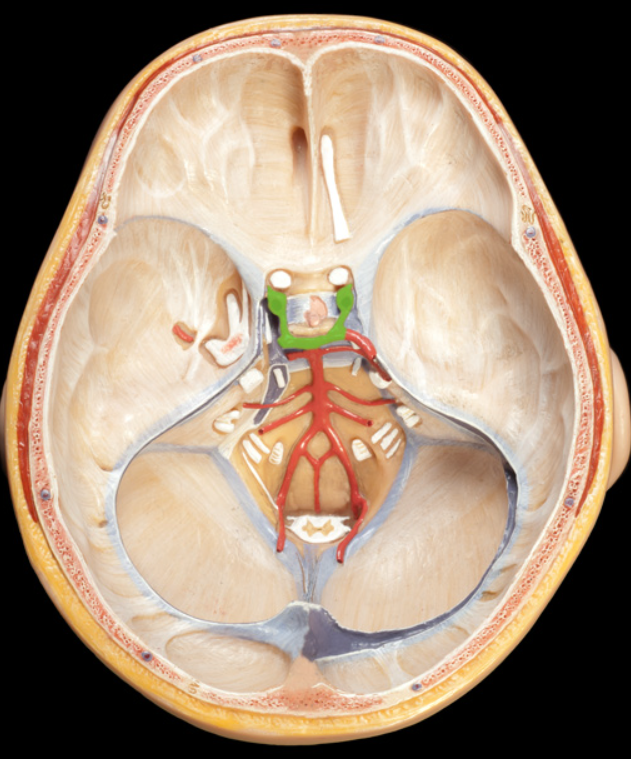

falx cerebri

falx cerebelli

tentorium cerebelli

dural sinus

vertebral arteries

New cards

Basilar artery

10

New cards

internal carotid arteries

11

New cards

Arterial circle